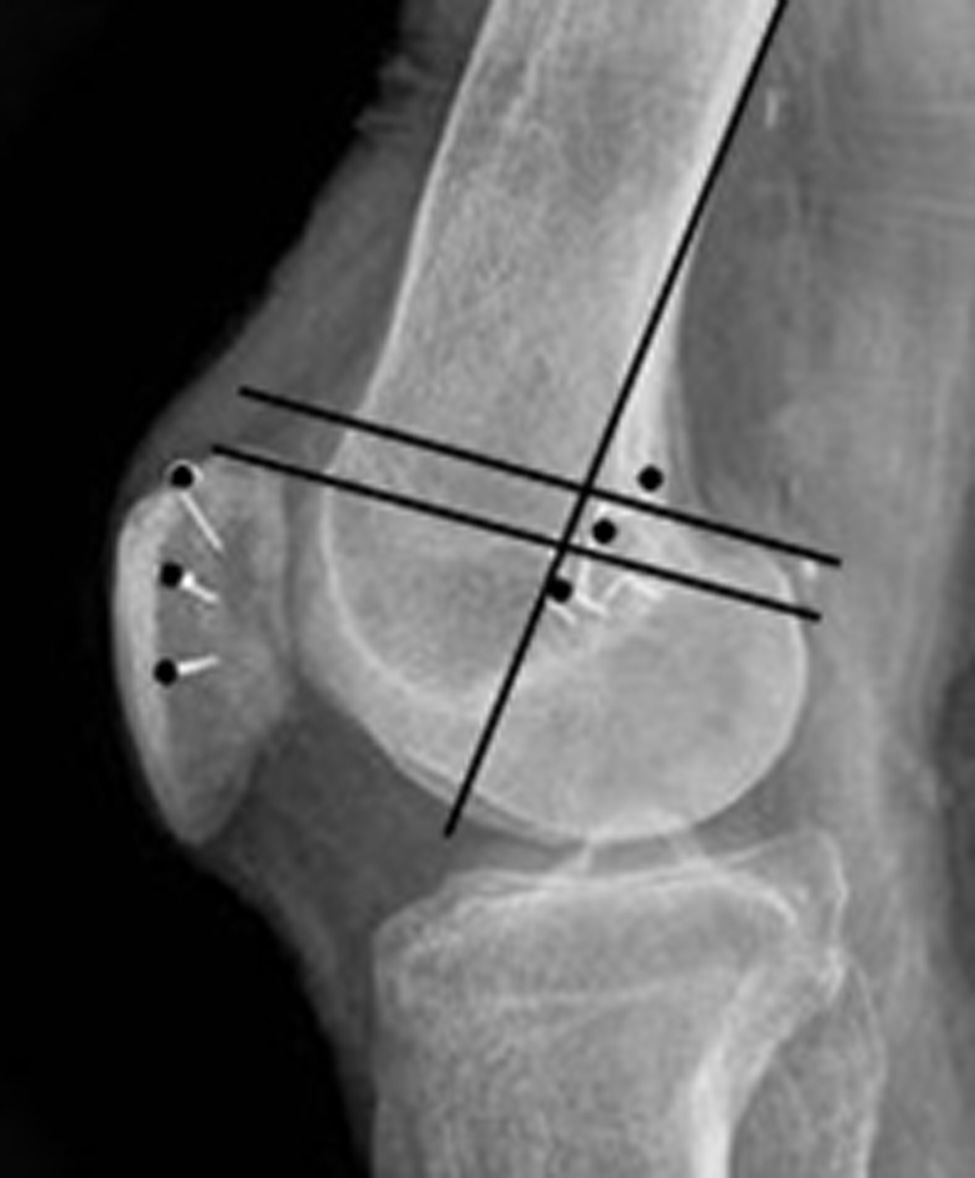

Måling af TTTG afstand (TTTG=Tuberositas Tibia Trochlea

Grove) er en mere præcis måling af Q-vinkel og malalignment:

Brug MR sagitale snit, kør ned til tuberositas og mål afstand fra midten af

tuberositas til kanten af billedet på skærmen. Gentag målingen fra midten af

troclea og træk de to tal fra hinanden. (Målet i eksemplet er 15,3 mm)